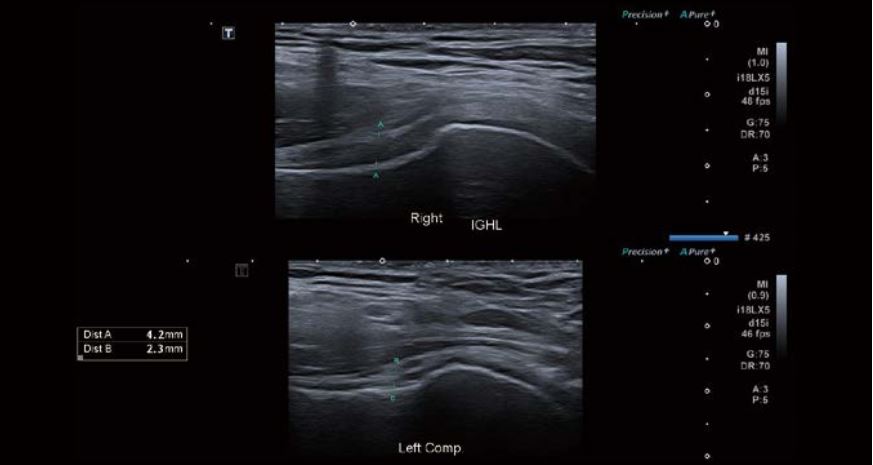

Було виявлено невеликий набряк оболонки сухожилля малого біцепса, потовщення та помірну васкуляризацію проміжку обертальної манжети. Спостерігалося незначне потовщення та асиметрія правої нижньої плечової зв'язки (НПЗ) та підпахвинної западини порівняно з лівою стороною. Товщина суглобової сумки була в межах норми, а в сухожиллях обертальної манжети спостерігалися мінімальні вікові зміни.

Зображення 2 Подвійний екран Canon демонструє, що IGHL дещо товстіша справа порівняно з безсимптомним лівим боком.